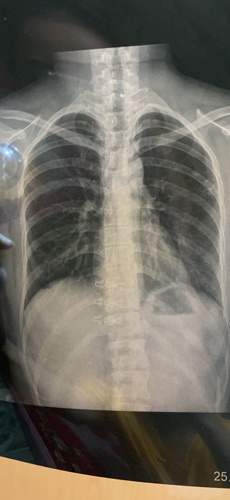

E bị sau covid đã hơn 3 tháng. Nhưng triệu chứng mệt mỏi thở hụt hơi và mệt hơi thở vẫn kéo dài suốt ngày . Mặc dù e di khám o nhiều viện bs chỉ chuẩn đoán bị tổn thương cũ o phổi thôi. K ghi nhận tổn thương mới. Nhưng e lại bị nặng ngực . Nhói tới sau lưng. Mệt hơi thở rất nhiêud . Spo2 lúc nào cũng 95-96 trở lên ạ. E lam tất cả xét nghiệm cũng bình thường. Bs cho e hỏi khi nào thi mới hồi phục lại và e có thể thở bình thường k mệt nữa ạ! Tâm lý e rất k ổn vì còn con nhỏ. Rất mong dc bs giúp . E 26 tuổi . K bệnh nền . Sức khoẻ trc đây tốt . Và đã tiêm 2 mũi vacxin trước khi mắc covid ạ! Vẫn bị hậu nặng nề như vậy . E di khám uống nhiều thuốc cũng k giảm ạ

E đang uống toa này bs . Vì hôm trc mệt quá nên đi vào cấp cứu truyền nước xong bs cho toa mua thuốc uống. Cũng k đỡ bs . Và bs nge tim phổi thì trong và tốt . Mà k hiểu sao e vẫn mệt theo kiểu nặng ngực với hơi thở suốt ngày.